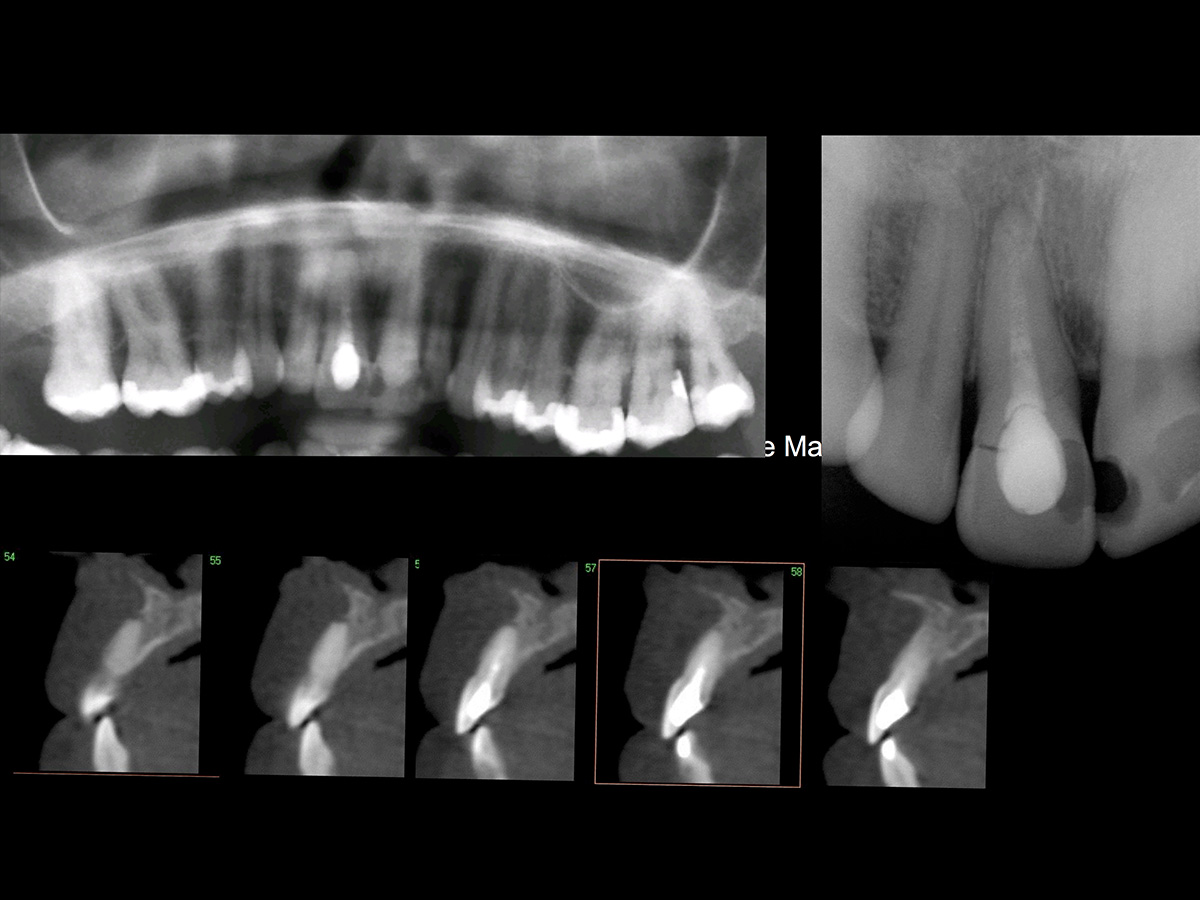

Der 38 Jahre alte Patient stellte sich in der Praxis mit Schmerzen in der Oberkieferfront vor. Die klinische Ausgangssituation lässt den Defekt aufgrund der Entzündung nur erahnen (Abb. 1). Der wurzelkanalbehandelte Zahn 11 musste wegen mehrfacher Frakturen extrahiert werden. Die Resorption des Knochens durch die endodontische apikale Läsion und die Entzündung führte zum kompletten Verlust der bukkalen Lamelle (Abb. 2).

Die dreidimensionale Aufnahme verdeutlicht den nach der Extraktion des Zahns zu erwartenden Defekt. Trotz schonender Extraktion, ohne aufzuklappen, konnte das Fehlen der knöchernen bukkalen Lamelle ertastet werden. Es folgten die Präparation und die Erweiterung des Implantatbetts. Die palatinale Positionierung von Implantaten liefert in der Regel gute Ergebnisse hinsichtlich der Implantaterfolgsrate, der Stabilität des periimplantären Gewebes, des Knochenverlusts und der Patientenzufriedenheit. Das Implantat ließ sich in der idealen Position primärstabil inserieren. Zur Regeneration der knöchernen Lamelle wurde die Bone-Lamina-Technik verwendet: Es wurde ein Mukoperiostlappen mit dem Tunnelinstrument präpariert, um die porcine kortikale Knochenmatrix (Osteo- Biol Soft Cortical Lamina, Tecnoss) einbringen zu können. Die Präparation wurde minimalinvasiv und ohne Inzision durchgeführt. Die Distanz zwischen dem palatinal inserierten Implantat und der bukkal eingebrachten Bone-Lamina füllten wir mit resorbierbarem knochenregenerativem Material, der deproteinierten bovinen Knochenmatrix OsteoBiol mp3 (Tecnoss), auf. Vor dem Eingriff wurde eine Funktionsanalyse durchgeführt und Meistermodelle wurden angefertigt. Da das Implantat sehr primärstabil eingebracht werden konnte, wurde direkt nach der Operation ein Abformpfosten gesetzt und mit einem Index versehen. Dadurch kann ohne eine Abformung die exakte Implantatposition dem Zahntechniker übermittelt werden. Postoperativ wurde der Patient instruiert, dreimal täglich mit 0,2 % Chlorhexidindigluconat bis zur Nahtentfernung zu spülen. Zusätzlich wurden für drei Tage Ibuprofen 600 mg, Amoxicillin und Clavulansäure verschrieben.

Abbildung 1

Ausgangssituation

Abbildung 2

Die Resorption des Knochens durch die endodontische apikale Läsion und die Entzündung führte zum kompletten Verlust der bukkalen Lamelle.